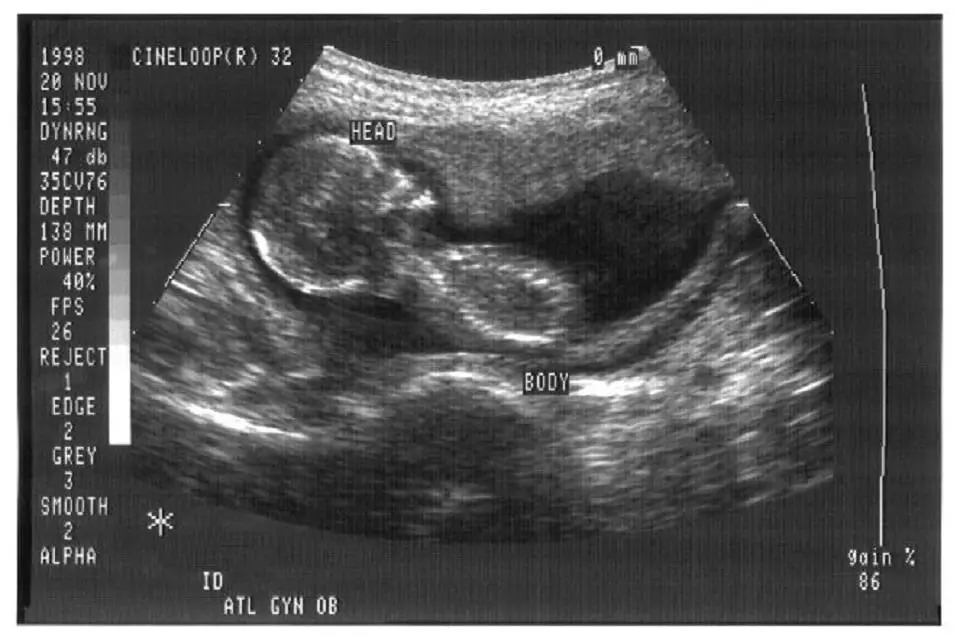

13, her mother was standing outside in the parking lot, begging a woman at a new. The test can help a healthcare provider diagnose. What is a pregnancy ultrasound?